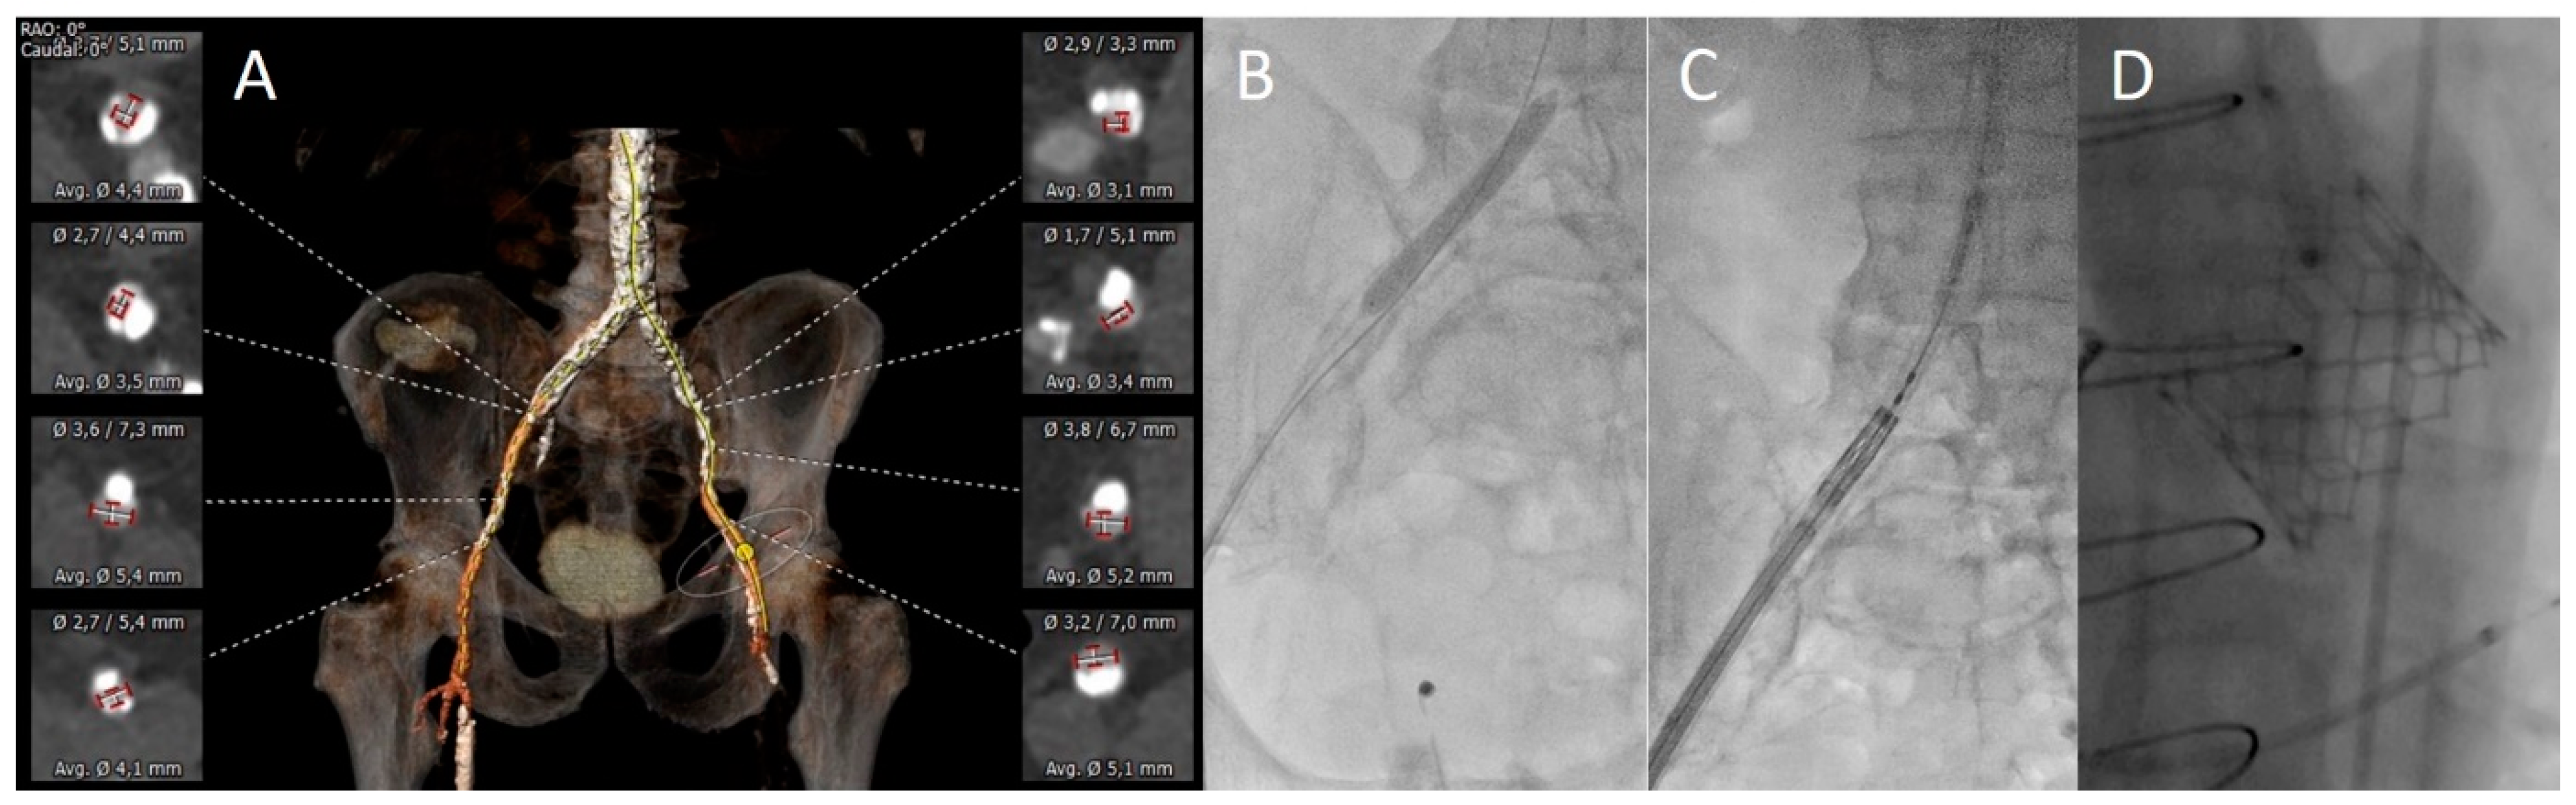

3.2. Vascular Assessment

3.3. Procedural Aspects